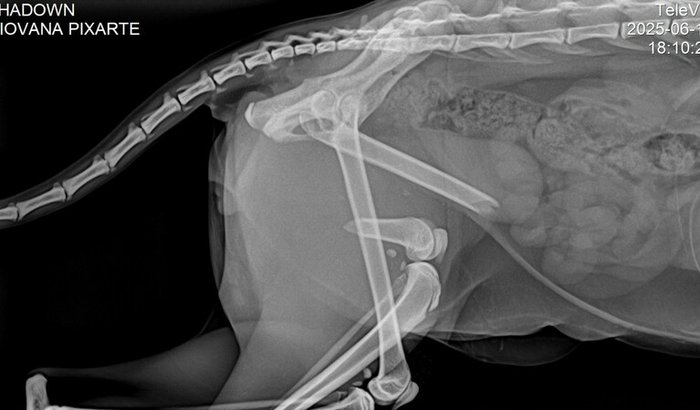

Meu nome é Gilvania, tenho um gato que se chama Sheldon, e na data de 18/06, ele fugiu de casa e depois de um tempo que fiquei chamando ele, apareceu todo machucado, percebi que tinha sido atropelado, peguei ele no colo e já percebi que estava com a pata esquerda traseira mole sem movimento, temperatura quente, e com o osso quebrado aparecendo em baixo da pele, dava pra sentir. Mesmo sem ter condições levei até o veterinário ele avaliou, e ficou até a noite pra fazer exame de raio x e ficar em observação. Depois que saiu o laudo do exame do raio x o veterinário me chamou e me disse que realmente ele tinha fraturado o fêmur esquerdo e que precisa passar por cirurgia ortopédica para correção, me passou orçamento, porém não tenho condições financeiras de arcar com os custos do procedimento cirúrgico que ficou no valor de 2380,00. Para conseguir tirar ele de lá da clínica tive que parcelar mesmo sem ter condições a consulta o raio x e também a medicação para aliviar a dor, mas o veterinário disse que no máximo 5 dias poderia prescrever a medicação, pois é forte e pode comprometer os rins e o fígado. Preciso muito da sua ajuda, se não contribuindo conforme seu alcance financeiro, então compartilhando com seus contatos para conseguir o quanto antes arrecadar o valor.